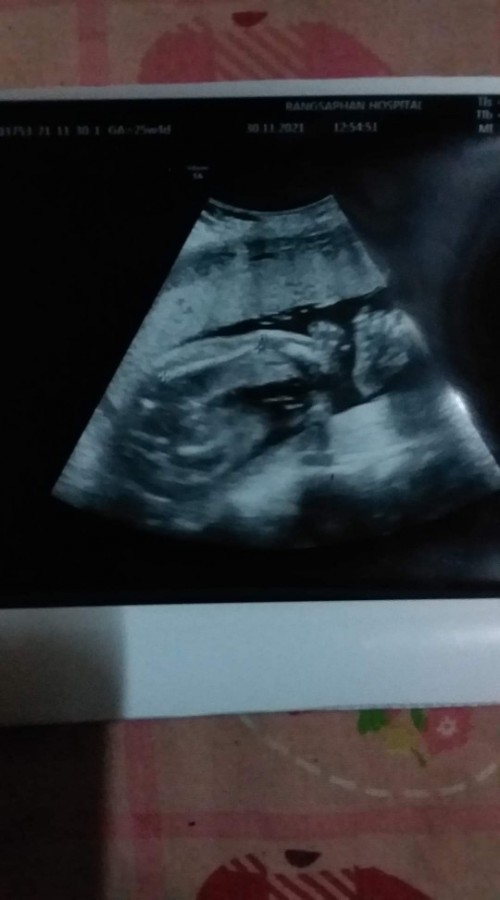

เพศ

ยังงี้มองออกไหมคะ ว่าเพศอะไร

ชายจ้าาา มาเต็มเลยลูก

ชัดมากแม่ 5555 ผู้ชายค่ะ

เหมือน ผช เลยจ้ะแม่ 😅

เหมือนเห็นไข่เลยค่ะ

ไข่ใหญ่มากแม่ ผชค่ะ

ชัดมากเลยจ้า ผู้ชาย

หนุ่มน้อย ผู้ชายค่ะ